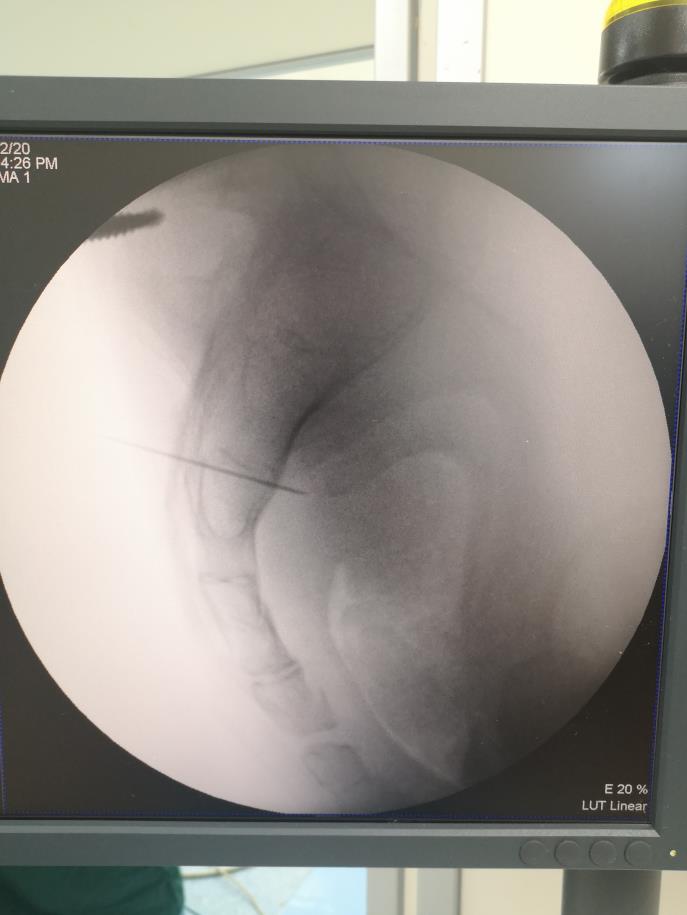

4月22日,孙主任团队在机器人辅助下,为王先生实施了骶神经调节术(I期),术中通过机器人辅助将患者骶骨及穿刺针用三维立体图像在计算机上完美呈现,确认穿刺针的进针方向、角度、深度后,测定穿刺定位点数据误差值为0.13mm,操作机器人进行骶3神经孔穿刺,只需一次,便可按程序将电极精准置入预先定位的位置。经治疗后,王先生腹胀、排便困难等症状明显改善。

如何将电极精准的置入?这是很多泌尿外科医生最关心的问题。孙主任说,以往通过“十”字X线定位法,术中来辅助进行骶3神经孔穿刺放置电极,部分患者需要多次调整穿刺针进针的体表穿刺点、角度及深度,并需要反复多次术中X线透视来确定电极置入的位置,所需时间较长,过程繁琐,增加穿刺区域感染的可能性,有的甚至影响I期测试效果,从而影响I/II期转化率。超声、3D打印的方法亦被辅助用于进行骶3神经孔穿刺定位,但因患者行超声定位或3D打印模板定位时体位与术中患者体位的影响,不能完美重合,骶3神经孔定位点处出现较大偏差而影响术中穿刺及I期测试治疗效果。